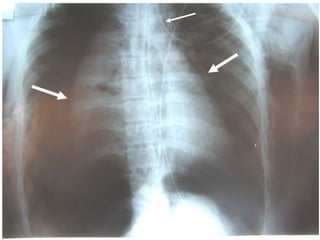

a- RX du thorax :

 clichés de face et de profil en inspiration profonde.

 RX de thorax de face en expiration forcée un  :

● épanchements minimes.

● La surveillance évolutive :total retour

du poumon à la paroi.

 Apports :

 Affirmer le pneumothorax.

 Définir le caractère complet ou incomplet du

pneumothorax

 Estimer la taille de l’épanchement.

 Analyser le parenchyme pulmonaire sous-jacent

et du coté opposé.

 Suivre l’évolution : retour du poumon à la paroi.

   Résultats :

Confirmation :

Hyperclareté homogène, avasculaire, périphérique,

Moignon hyperdense rétracté sur le hile,

Distension des EIC et une netteté anormale des cotes.

Plèvre viscérale :fin liseré opaque net comme tracé au

crayon.